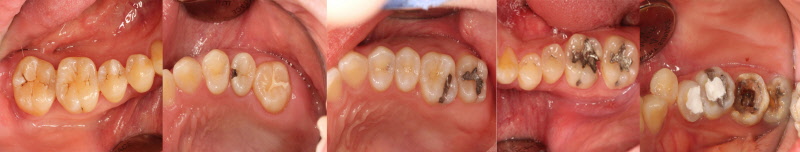

좌측의 초기부터 점점 진행되는 충치의 사례입니다. 제일 좌측은 치료받지 않고 두어도 무관한 정도이지만 가장 우측은 발치를 시행해야 하는 정도로 진행되어 있습니다. 충치는 명쾌하게 단계를 자를 수 있는 병이 아닌 점진적 진행으로 나타나므로 같은 정도의 충치라도 많은 변수를 고려해야 합니다. 의사마다 치료 방법과 방향이 다른 이유입니다. 각자의 경험과 생각하는 바, 앞으로의 예후와 환자의 조건들을 총 취합해서 평가해야 하니 같은 경우는 드물게 됩니다 .